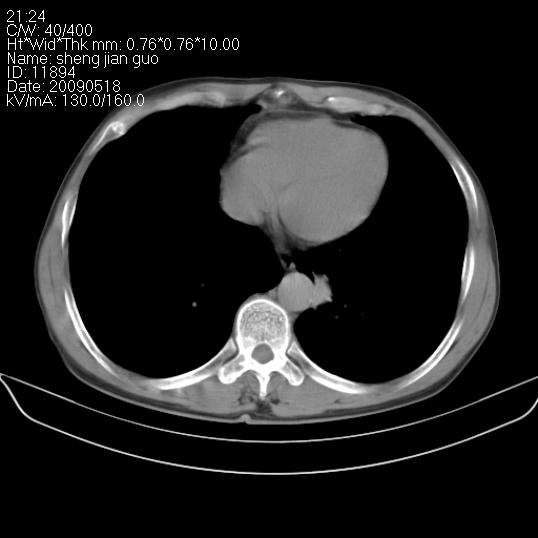

以下是引用zjzjr在2009-5-19 17:25:00的发言:[br]支持楼主考虑,另左肺下叶阻塞性炎症。

以下是引用zhao_bin2008在2009-5-19 17:48:00的发言:[br]支持左肺下叶周围型肺癌并阻塞性肺炎。

以下是引用zsl6918在2009-5-20 7:10:00的发言:[br]左侧中心型肺癌!